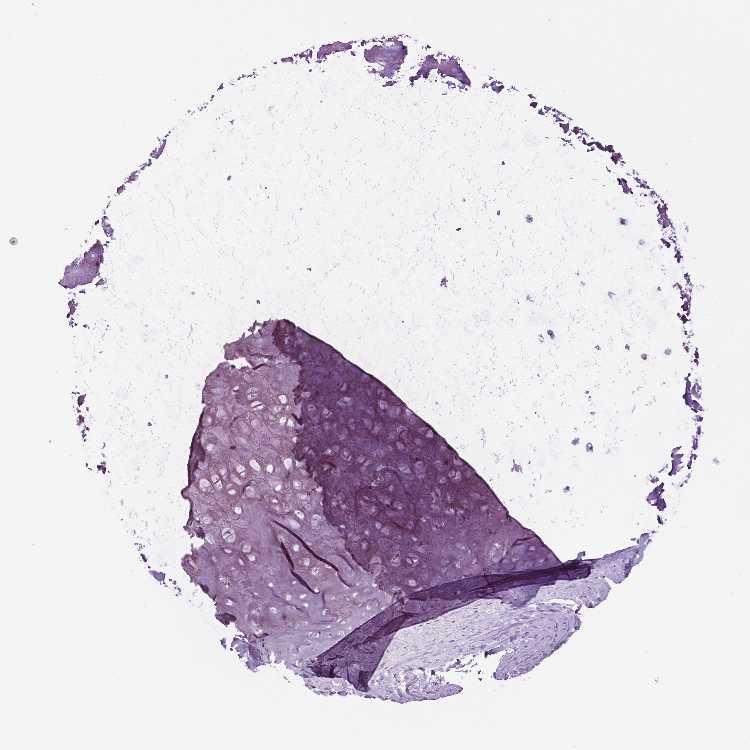

SOFT TISSUE 1 - Antibody stainingi

Antibody staining in the annotated cell types in the current human tissue is reported as not detected, low, medium, or high, based on conventional immunohistochemistry profiling in selected tissues. This score is based on the combination of the staining intensity and fraction of stained cells.

Each image is clickable and will lead to virtual microscopy that enables deeper exploration of all samples and also displays staining intensity scores, fraction scores and subcellular localization as well as patient and tissue information for each sample.

Antibody HPA010689

Chondrocytes Not detected

Fibroblasts Not detected

SOFT TISSUE 2 - Antibody stainingi

Peripheral nerve Not detected